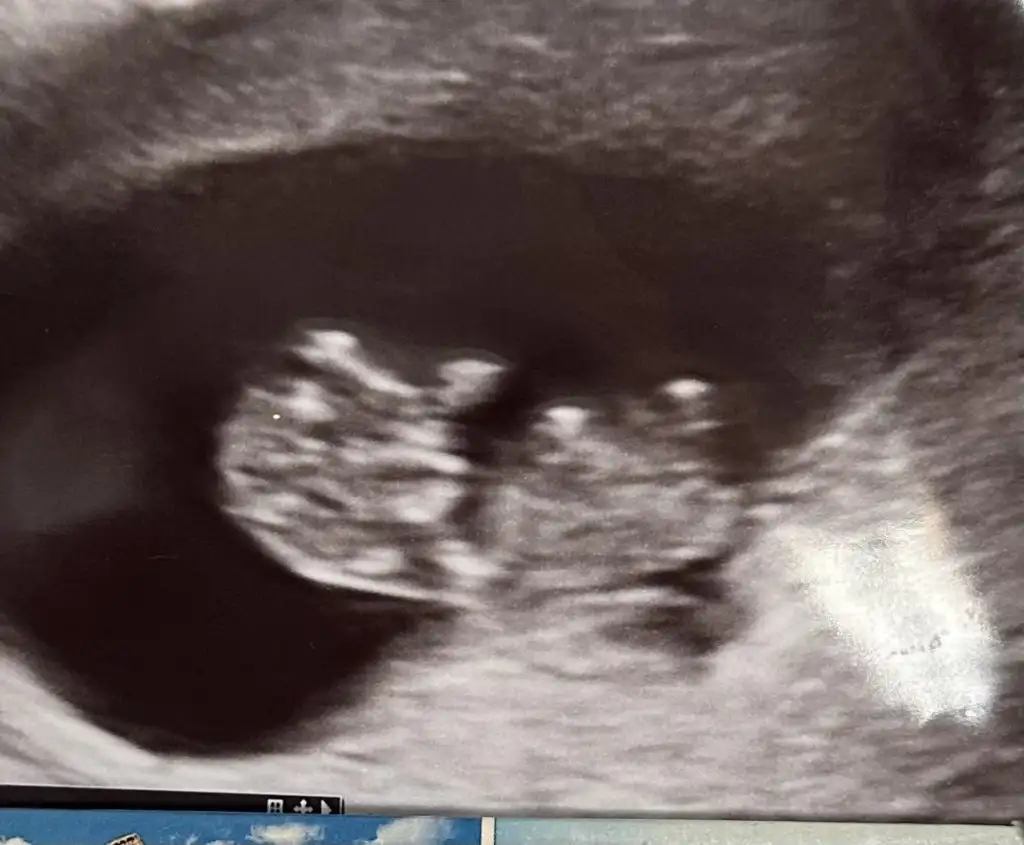

Bizede tahminde bulunur musunuz kızlar

Bence erkek çünkü kafa yapısı da erkek gibi bacak arası da